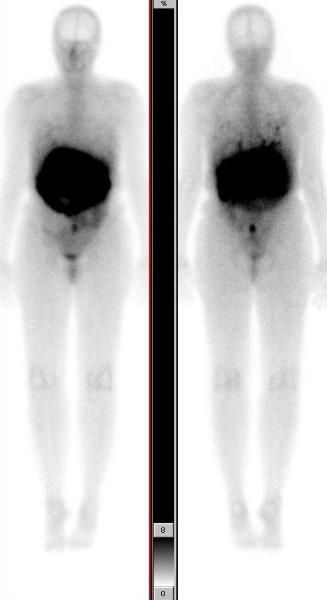

Images below show post therapy scans acquired 48 hrs after PRRT with 471.0 mCis of In-111 Octreotide. The anterior and posterior whole body scans are presented in two different intensities. They show good targeting with intense uptake in metastatic lymphadenopathy and uptake in bilateral lung nodules (scan shown in higher intensity).

This case illustrates the role of post therapy scan in confirming the metastatic etiology of bilateral lung nodules. These nodules did not show any uptake with the low dose of In-111 Octreotide used for diagnostic imaging, but were seen to take up In-111 Octreotide on the post therapy scan. This is likely due to higher radiopharmaceutical activity used for therapy, as compared to the diagnostic scan. This phenomenon is frequently seen in treatment of thyroid cancer patients with I-131, and comparing the I-131 post therapy scan with the diagnostic low dose I-131 scan.